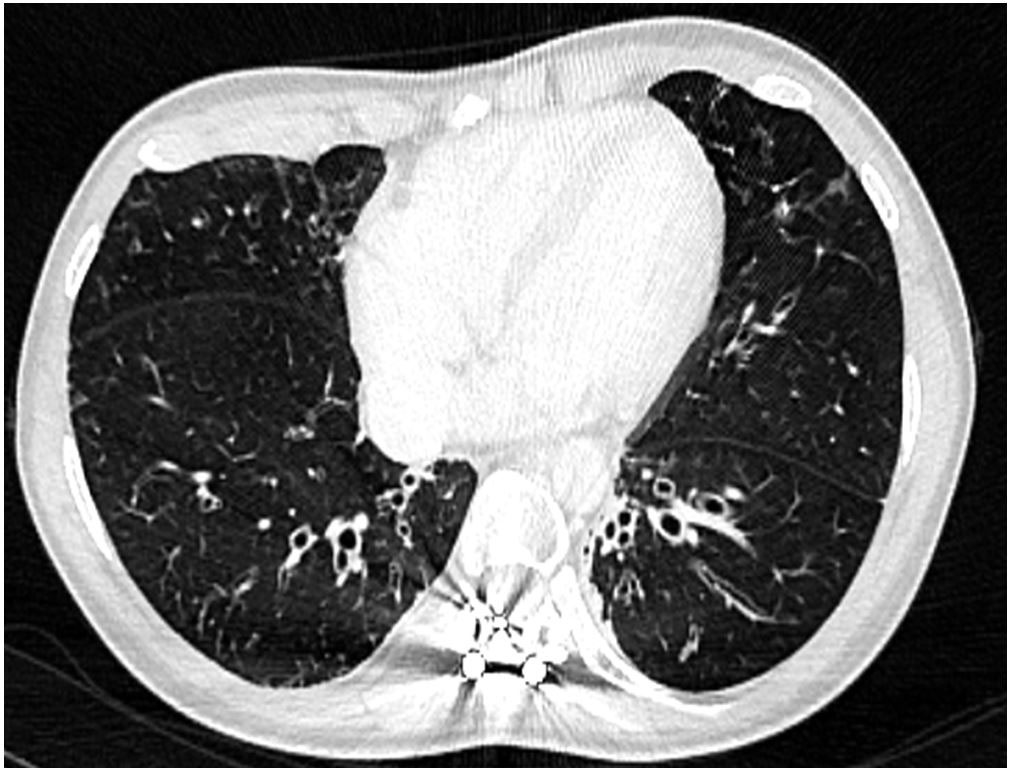

Figure 2 Thoracic computed tomography confirming the X-ray findings.

A 27-year-old female was referred to our department for management of an autoimmune haemolytic anaemia. Recent medical history included a diffuse large B-cell lymphoma at the age of 20 with negative Epstein-Barr virus (EBV) serology. She was considered in remission after four courses of rituximab, adriamycin, cyclophosphamide, vincristine, bleomycin, prednisone and intrathecal methotrexate, and consolidation with 2 infusions of methotrexate followed by successful autologous stem cell transplantation. During and after chemotherapy she had many bacterial infections and two episodes of herpes zoster reactivation. Examination of her childhood medical history found neonatal dwarfism and scoliosis with spinal osteosynthesis (fig. 1A), recurrent acute pulmonary and ear, nose and throat (ENT) infections with otitis media from the ages of 3 to 10 years, requiring placement of tympanostomy tubes at the age of 6 and adenoidectomy. The patient described frequent bronchitis and sinusitis requiring antibiotic courses two or three times a year, complicated by bronchiectasis (fig. 1B).